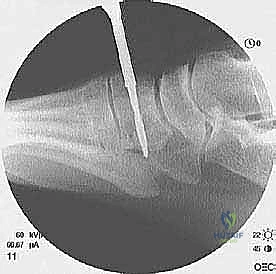

6. التثبيت العظمي المتين (Bone Fixation)

كيف نثبت الوتر الجديد؟ يقوم الأستاذ الدكتور محمد هطيف بحفر نفق عظمي دقيق في العظم الإسفيني الإنسي (Medial Cuneiform) في القدم. يتم إدخال وتر EHL داخل هذا النفق وتثبيته بقوة فائقة باستخدام إحدى التقنيات الحديثة:

* مسامير التداخل القابلة للامتصاص (Bio-absorbable Interference Screws).

* خطاطيف التثبيت العظمية (Suture Anchors).

يتم التثبيت والقدم في وضعية الانثناء الظهري الأقصى (مرفوعة للأعلى) لضمان الشد المناسب للوتر.